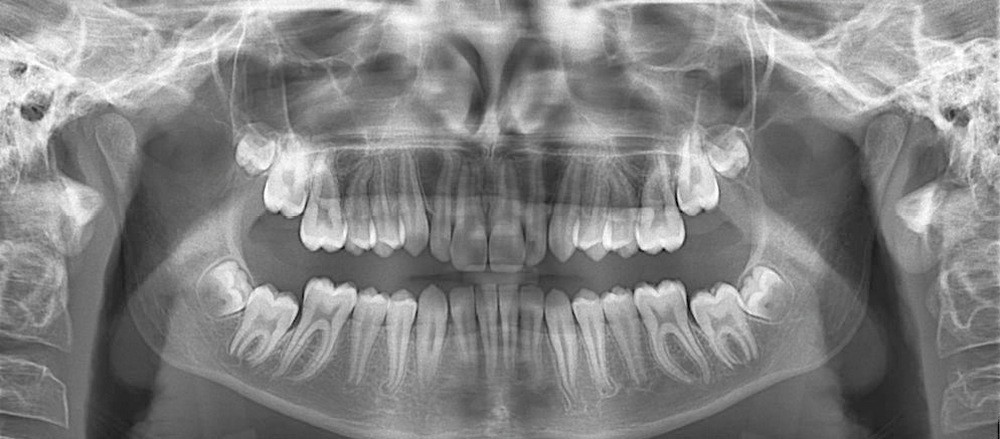

La formule dentaire est complète, avec un léger retard d’évolution des deuxièmes molaires (fig. 8).

La classe II squelettique est objectivée par l’angle ANB = 7,6° confirmée par l’AoBo = 7,6 mm l’étiologie étant d’origine mandibulaire SNB = 69,9° (fig. 9 et 10).